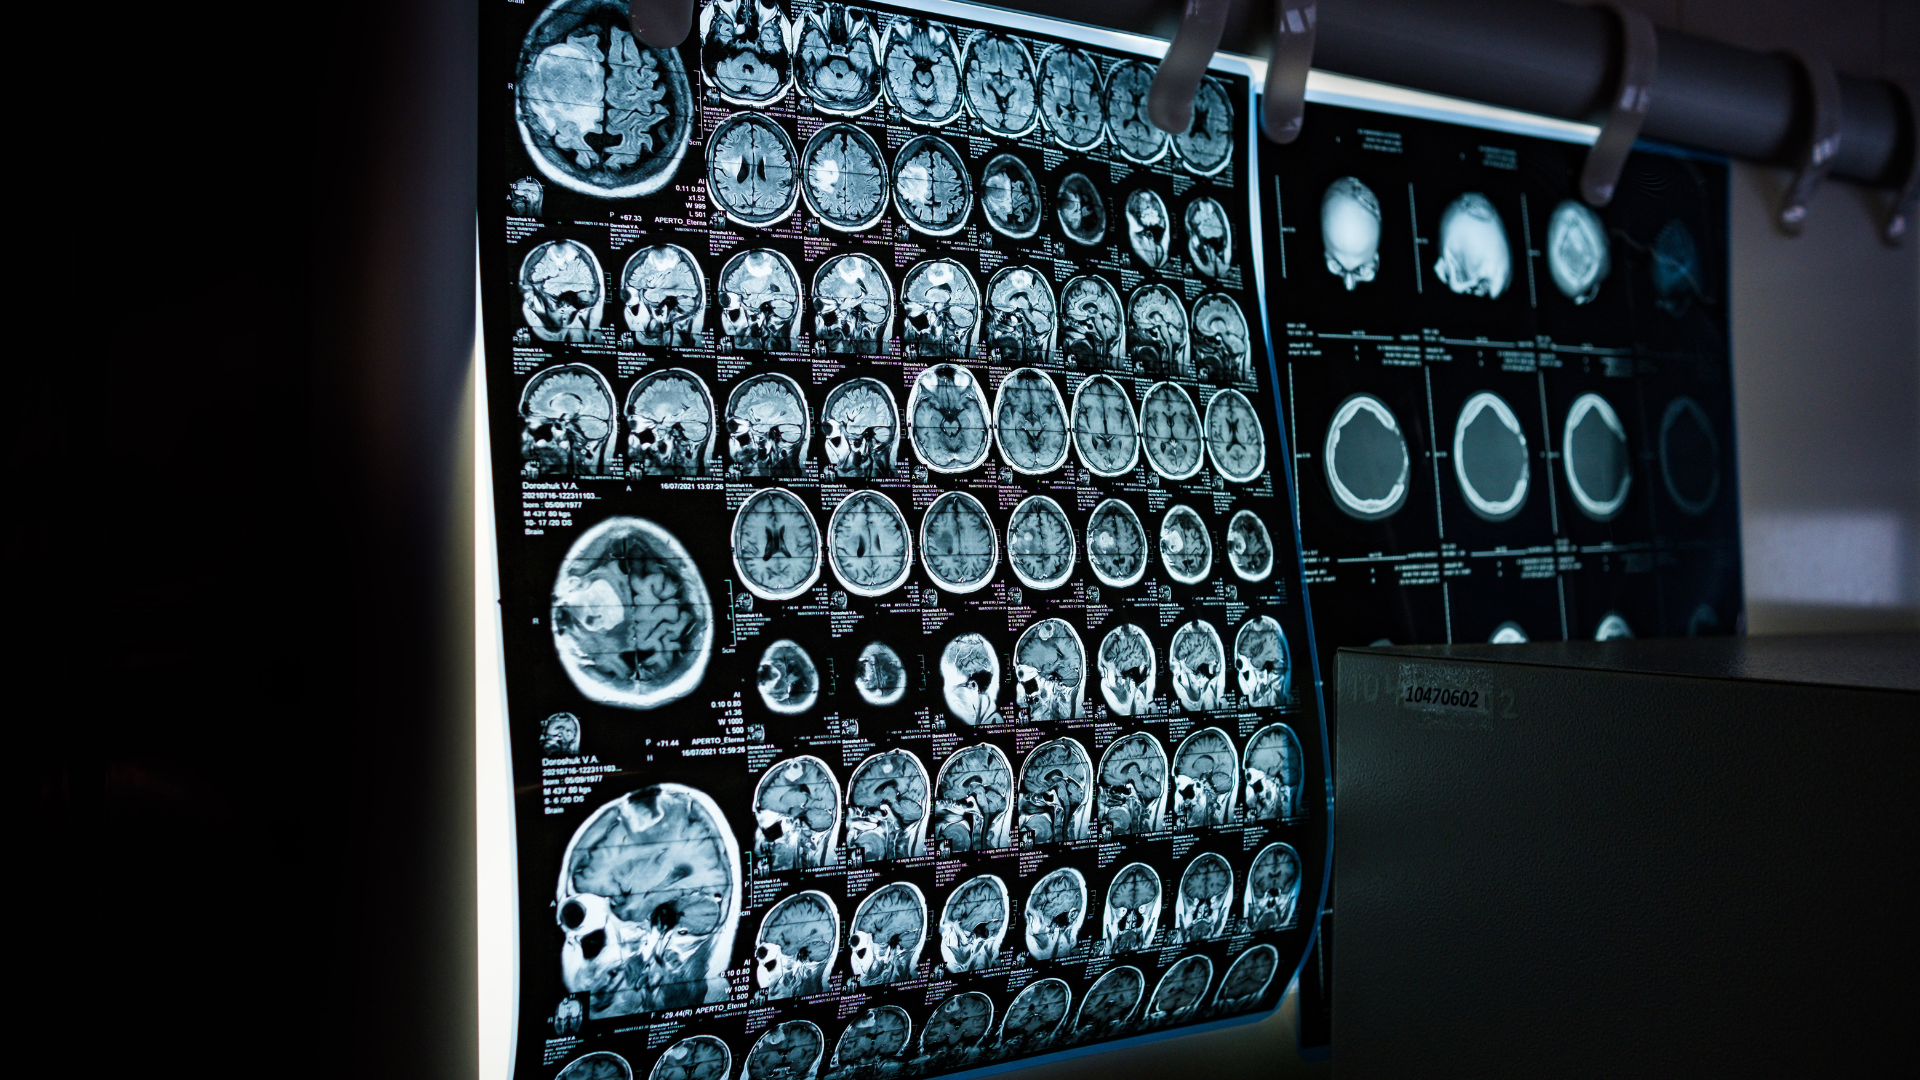

Đại não là phần lớn nhất của bộ não, chiếm phần trọng lượng lớn và đảm nhận hầu hết các chức năng tinh vi trong hệ thần kinh. Đây được xem là trung tâm xử lý thông tin và điều phối mọi hoạt động từ hoạt động thể chất đến tư duy phức tạp. Những suy nghĩ, cảm xúc, ngôn ngữ, ký ức đều có mối liên hệ mật thiết với hoạt động của đại não.

Đại não có cấu trúc phức tạp, được chia thành nhiều bộ phận khác nhau nhưng phối hợp nhịp nhàng để giúp cơ thể hoạt động hiệu quả. Mỗi phần nhỏ trong đại não đều đóng góp một vai trò riêng và không thể thiếu.

Vỏ não là lớp ngoài cùng của đại não, có bề mặt gấp nếp nhằm tăng diện tích hoạt động. Đây là nơi diễn ra nhiều chức năng cao cấp như xử lý thông tin cảm giác, ra quyết định, tư duy, ghi nhớ và ngôn ngữ.

Vỏ não có thể được xem là trung tâm xử lý các dữ liệu đến từ thế giới xung quanh và bên trong cơ thể, chuyển hóa chúng thành các phản ứng phù hợp.